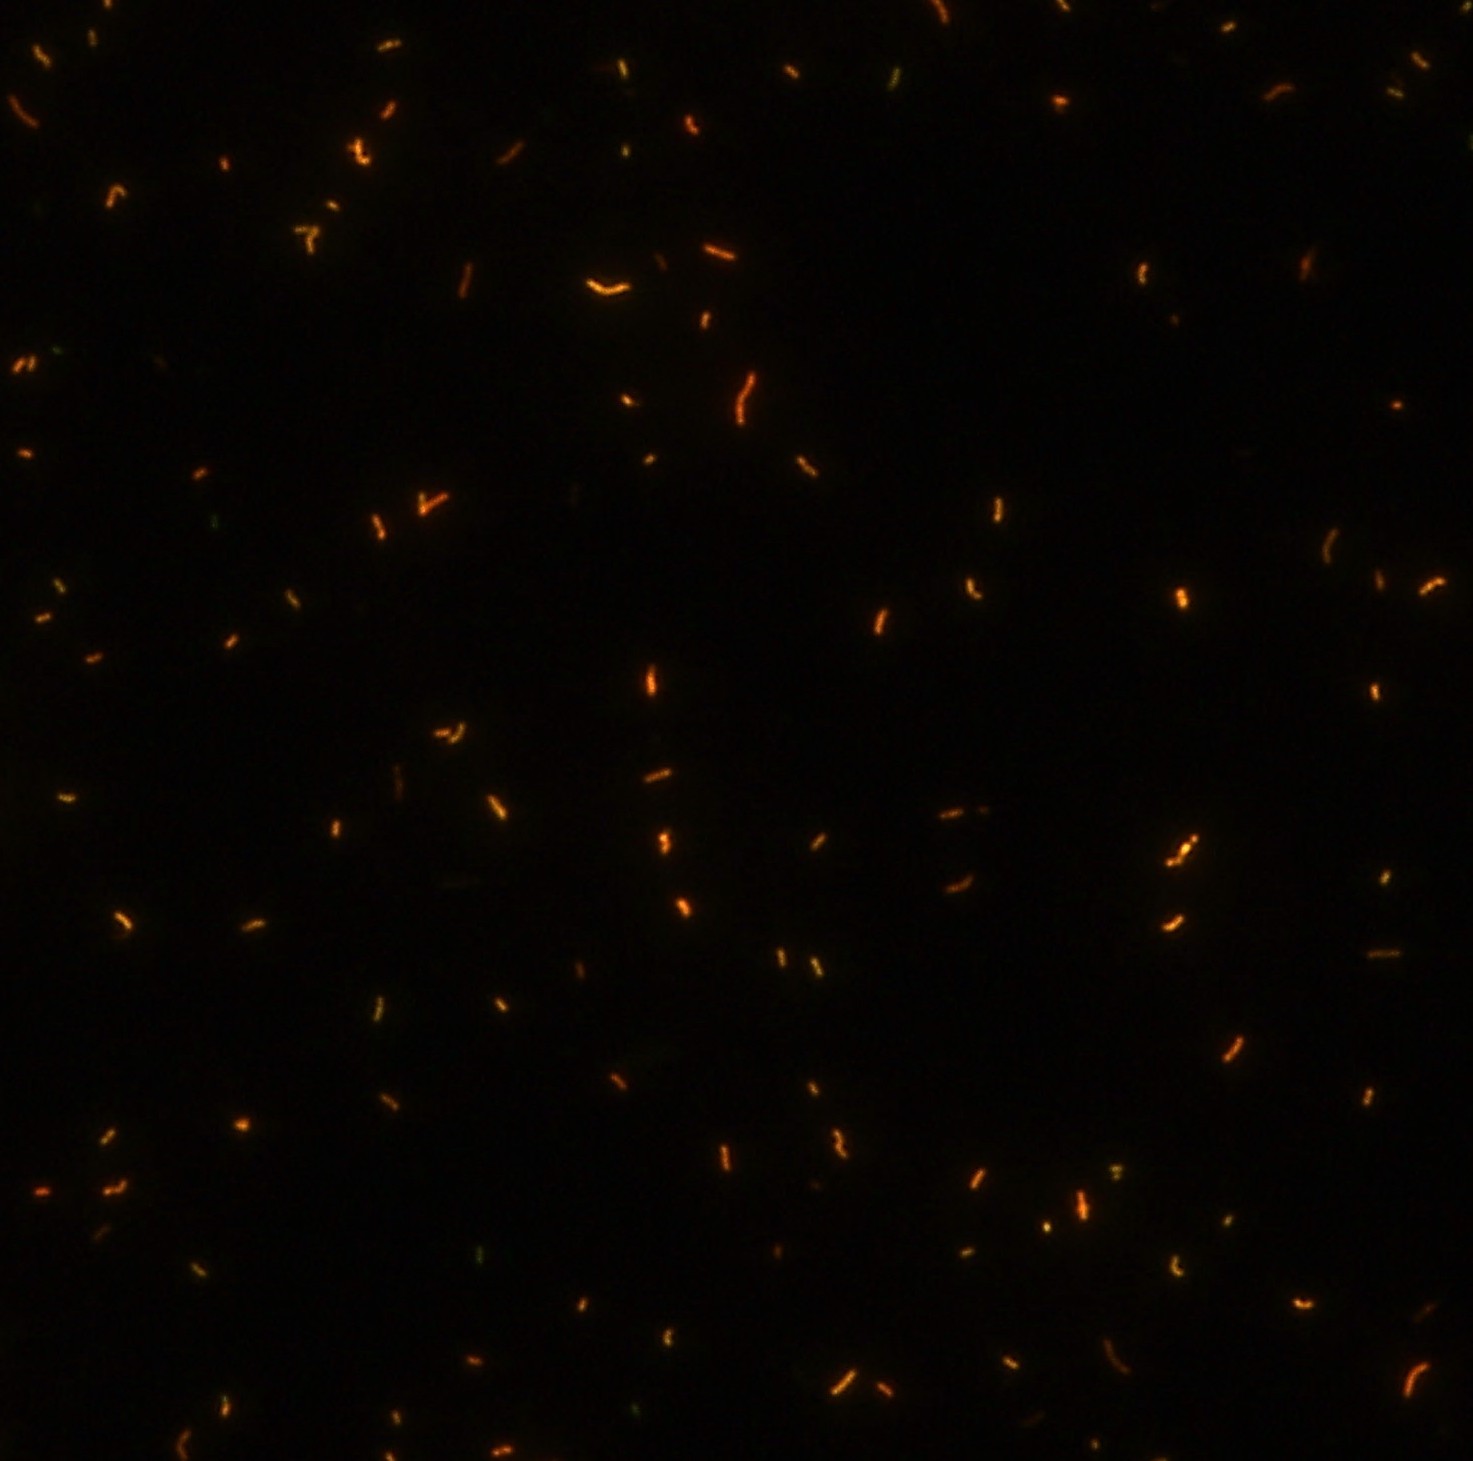

顯微染色技術(shù)是檢測結(jié)核桿菌方法之一。分枝桿菌細胞壁中含有分枝菌酸,其可以與染料牢固結(jié)合,具有“抗酸性”的特征。熒光染料金胺-羅丹明在染色中與抗酸生物細胞壁內(nèi)的分菌酸相結(jié)合,并耐受酸醇(脫色劑)清洗脫色。反染色劑高錳酸鉀被用來顯出染色生物。AFB(熒光)染色試劑盒設(shè)計既可用于染色機,也可用于手工染色。產(chǎn)品穩(wěn)定性好,染色效果佳。

染色結(jié)果 熒光法×400

用于分枝桿菌、諾卡菌等細菌抗酸染色,包括熒光染色。